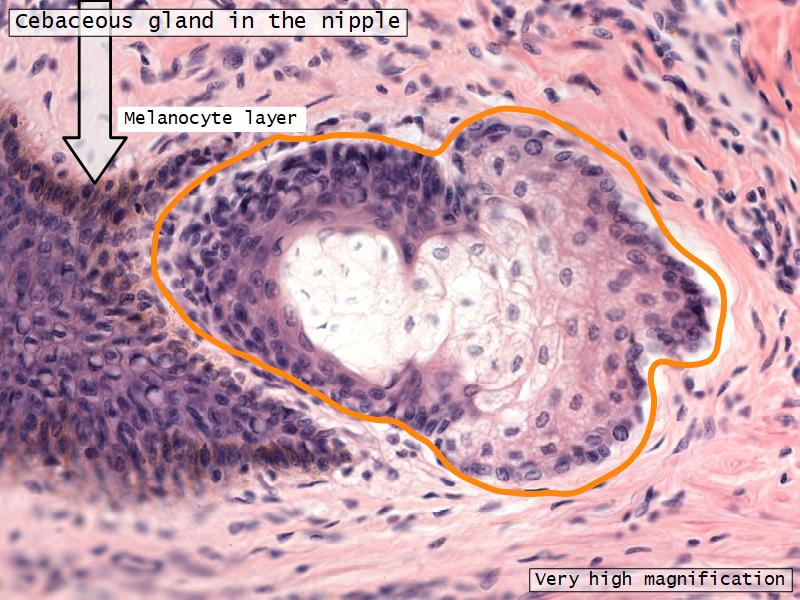

What are the main morphological features of the nipple?

Morphology

Skin

- Keratinized stratified squamous epithelium

- Sebaceous glands